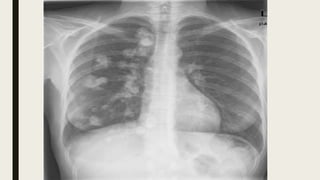

■ X ray of lungs show white shadow and cause

respiratory deficit

EFFECTS OF METASTATICCALCIFICATION ■ X ray of lungs show white shadow and cause respiratory deficit ■ Massive deposits in kidney (nephron calcinosis)can cause stones and renal damages